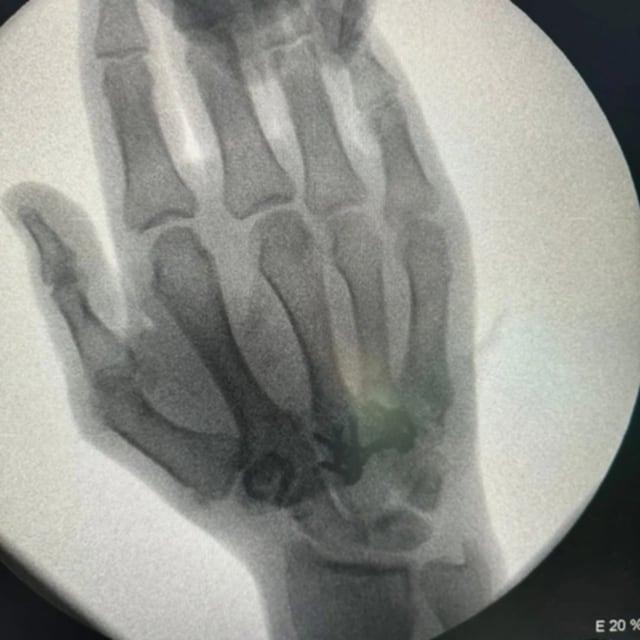

Tokio-2020 Yay Olimpiya Oyunlarının gümüş mükafatçısı, karateçi Rafael Ağayev əl və burun nahiyəsindən əməliyyat olunub.

İdmançımız hazırda vəziyyətinin yaxşı olduğunu, əməliyyatın uğurlu keçdiyini bildirib.